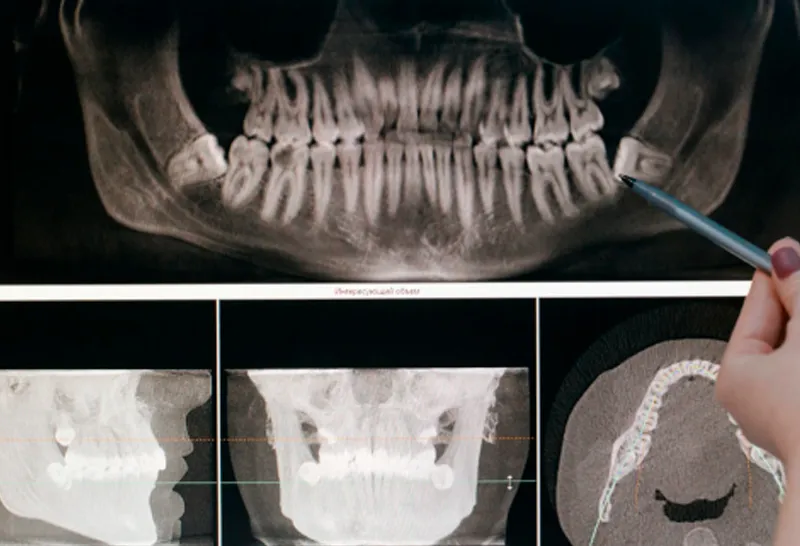

Análise de exames de imagem (ênfase em tomografia)